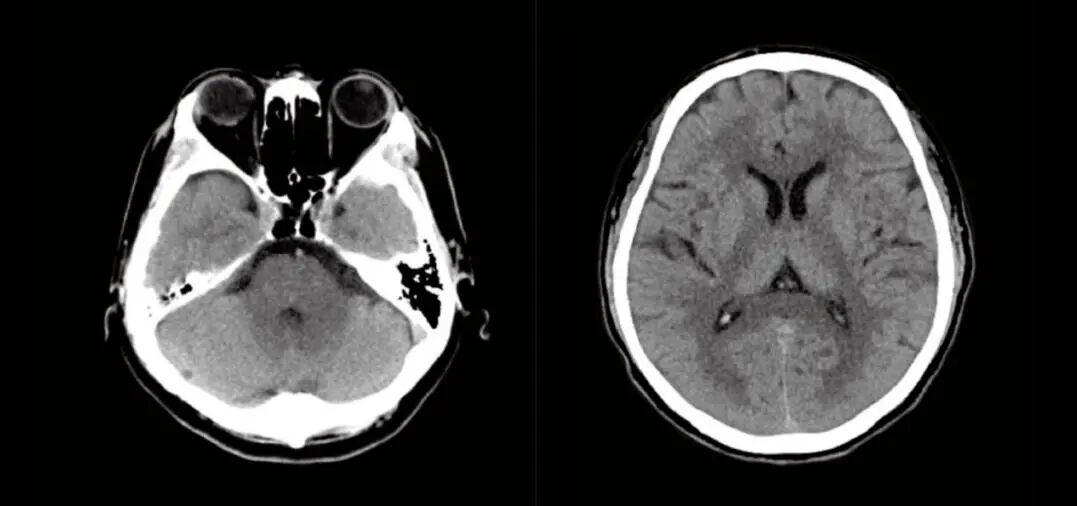

7、颅脑CT检查:是一种检查方便,迅速安全,无痛苦,无创伤的新的检查方法,它能清楚的显示颅脑不同横断面的解剖关系和具体的脑组织结构。因而大大提高了病变的检出率和诊断的准确性。